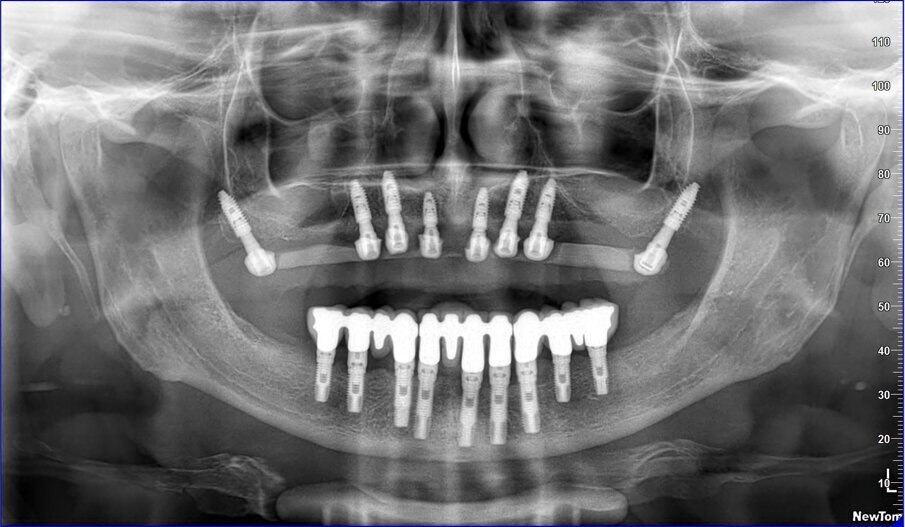

Gli impianti vengono distribuiti lungo tutta l’arcata cercando il parallelismo e limitando il più possibile i cantilever (6-7 impianti superiori e 5-6 impianti inferiori). La scelta di utilizzare i monconi dritti (grazie al parallelismo degli impianti) è da preferire in quanto quest’ultimi sono anche i più robusti e resistenti nel tempo al carico assiale; inoltre caricano l’impianto lungo il suo asse limitando i carichi disassati. Una volta elevato il lembo mucoperiosteo ed evidenziato l’osso alveolare o basale, attenzione deve essere fatta nel fare un’ostectomia riduttiva mediante una fresa a palla del diametro di 0,6-0,8 cm per creare un piano più uniforme possibile tale da formare una piattaforma d’osso alla stessa altezza, guadagnando anche spessore V-L ed uniformità. Gli impianti devono essere posizionati alla stessa altezza tra di loro e distanziati in maniera tale da favorire le manovre di igiene orale inter-implantare. Una volta posizionate le fixture sottocrestali (1-3 mm) come descritto, vanno connessi i monconi solitamente con collare mucoso di 3-4,5 mm in altezza, ponendo particolare attenzione che i tessuti molli suturati non coprano la parte di accoppiamento conometrico. Verificato il parallelismo corretto dei monconi mediante i pin parallelizzatori, siamo certi che l’accoppiamento e la disconnessione delle cappette contenute nella protesi potrà avvenire nel miglior modo possibile senza creare tensioni.

La resina alla stato ancora tenero va indurita con la lampada polimerizzante per alcuni minuti; una volta controllata la masticazione anche senza la chiave articolare e fatti gli opportuni minimi ritocchi, la protesi va rimossa e rifinita a dovere, poi riaccoppiata. Una OPT di conferma serve per verificare il corretto alloggiamento delle cappette sui monconi e la passività del manufatto.

Le tabelle 1-8 mostrano, su un totale di 313 impianti eseguiti tra arcata superiore (208) e inferiore (105), che la tecnica non ha alcuna complicanza biologica a 3 anni di esecuzione, non sono stati evidenziati fallimenti implantari in arcata inferiore (18 pazienti), solamente 5 in arcate superiori tutti nella zona molare (29 pazienti). In 1 paziente è stata registrata una frattura della protesi dovuta a eccessiva distanza tra gli impianti (zona laterale superiore e tuberosità) con antagonista naturale senza presenza di molari; 3 fratture dei denti in pazienti con bruxismo e serramento; circa la metà dei casi (140 impianti) è stata eseguita in condizione post-estrattiva e alcuni casi sono stati caricati con metodiche avanzate di rialzo di seno mascellare (11 pazienti) e 1 con Split Crest. Tutti gli impianti sono stati caricati immediatamente, anche quelli nei settori posteriori superiori o nella tuberosità.